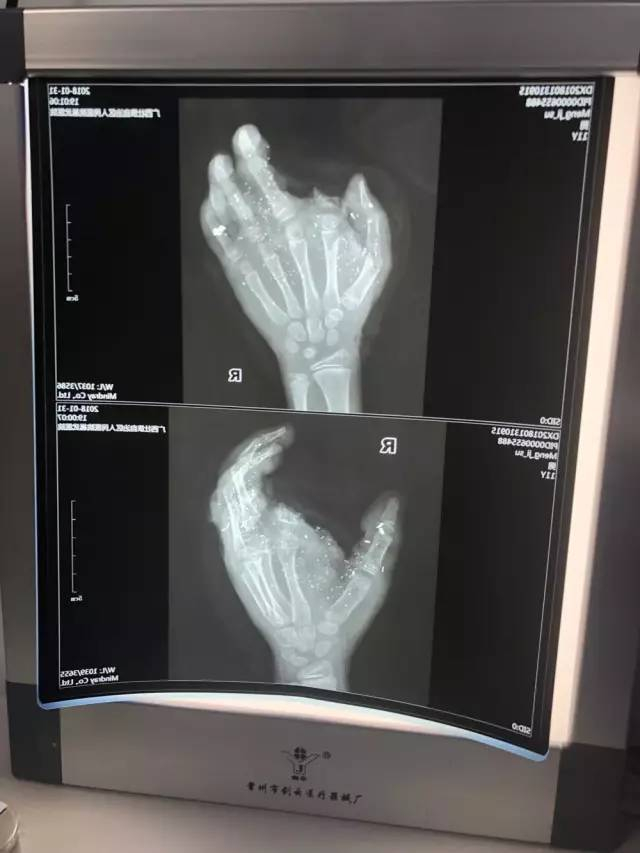

经检查发现

小明眼球有异物

肺部挫伤、右手臂和手指粉碎伤,食指断离

▼

医生马上安排孩子

前臂皮瓣转移修复术、拇指、中指、环指再植手术

手术直至当天凌晨5点才完成

除了食指无法接回,其他四根手指都接回来了

目前小明的手掌已经恢复供血

有98%的痊愈率,恢复功能没有问题